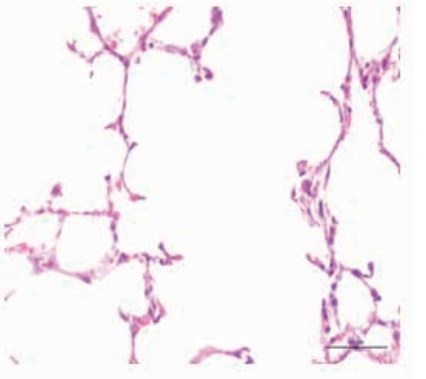

Lung microphotograph - normal

Lung microphotograph after 16 weeks of smoke

Lung microphotograph after 16 weeks of smoke and Vitamin D

Far less inflammation @ 16 weeks in mice getting Vitamin D

Almost as low inflammation as "non-smokers"

Cigarette smoking is known to induce serious lung diseases, but there is not an effective method to solve this problem. The present study investigated vitamin D3 on over-expression of CXCR3 and CXCL10 in mice induced by cigarette smoking. A pulmonary airway model was designed, and morphological assessment of emphysema, IL-4, IFN-γ and CXCL10 concentration in bronchoalveolar lavage fluids, expression of CXCR3 and CXCL10 were detected. Emphysema of the mice only exposed to cigarette smoke was significant, and concentration of IL-4, IFN-γ and CXCL10 was also increased. In addition, CXCR3 and CXCL10 were over-expressed. The degree of emphysema, concentration of IL-4, IFN-γ and CXCL10, and expression of CXCR3 and CXCL10 in mice administrated with low dose vitamin D3 were similar to the normally treated mice. Low dose of vitamin D3 can effectively protect the lung from the damage induced by cigarette smoke.